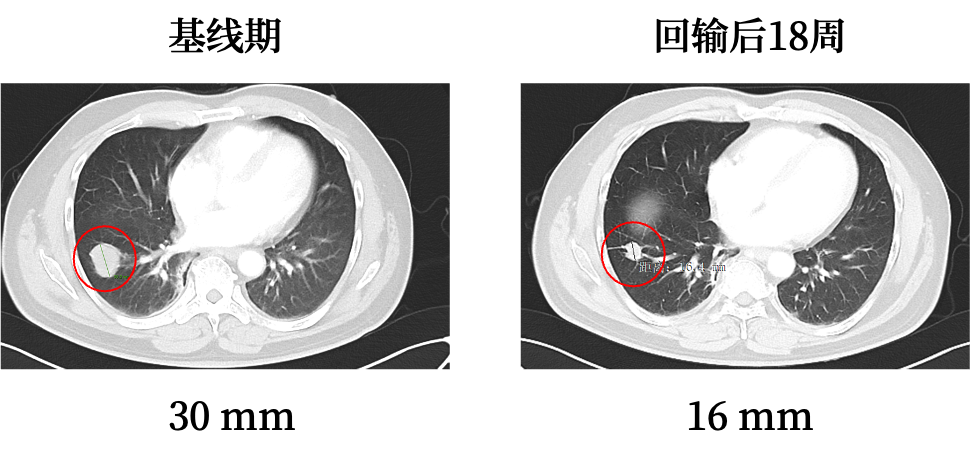

非常幸运,该患者就诊的医院当时正在进行君赛生物GC101的临床试验,患者毅然参加了GC101临床试验项目。接受回输后,未观察到明显不良反应,整体耐受性良好。回输后未接受其他治疗的情况下,肿瘤持续缩小,18周时肿瘤影像学评估,疗效为部分缓解(Partial Response,PR)。